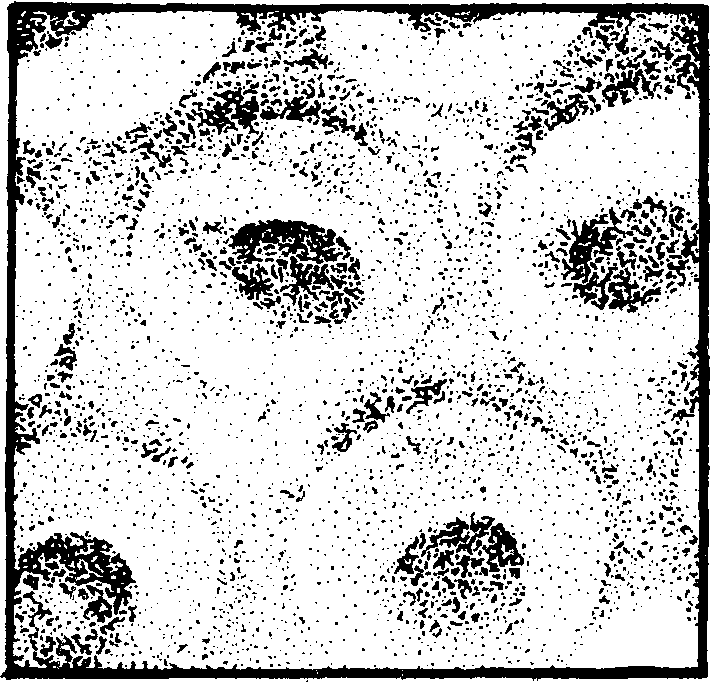

图1.4-1 正常人的红细胞的立体形态(立体电子显微镜照相)

红细胞(简称RBC)是血细胞中最多的一种。成熟的红细胞呈双凹圆盘形(见图1.4-1),直径约为8微米,周边较厚,中心较薄,无细胞核。男性每立方毫米血液中红细胞数为450—550万个(平均500万个),女性约为380—460万个(平均420万个)。红细胞内含有红色的血红蛋白(简称Hb),因而血液呈红色。血红蛋白约占红细胞重量的32%。男性每100毫升血液中含有血红蛋白12—15克,女性含有11—13克。红细胞运输氧的能力是由其中的血红蛋白实现的。血红蛋白中的Fe2+能在肺内(氧分压高)与氧结合为氧合血红蛋白,在组织中(氧分压低)又将氧放出,成为还原血红蛋白。红细胞中的血红蛋白还有运输二氧化碳的能力。